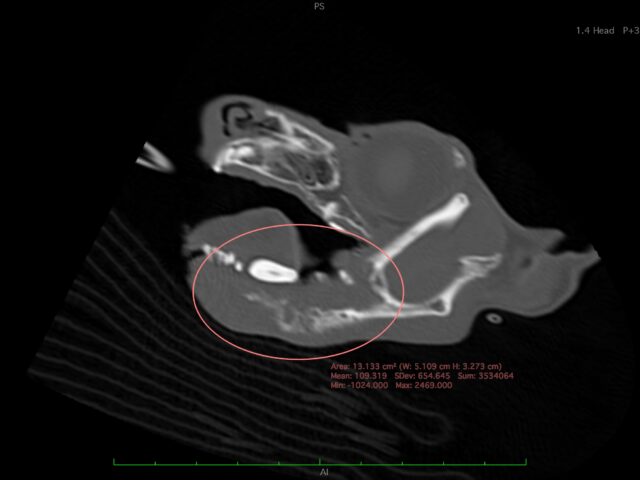

01 高度医療

動物用CTを用いた検査が可能です。経験豊かな獣医師が患者様の状況に合わせて最善の検査・治療をご提案いたします。また、軟部組織外科など難度の高い手術症例にも対応しています。